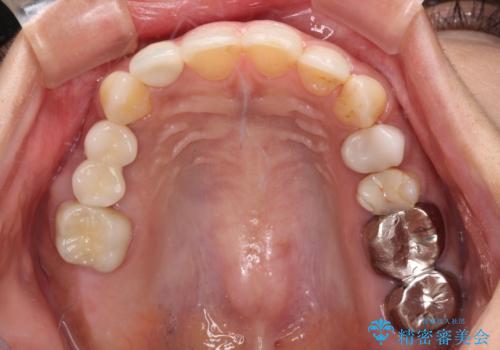

レントゲン写真などで診査した結果、奥歯の銀歯の下にはむし歯が多く存在し、右上の奥歯は歯根が破折していました。

破折した歯を抜去し、インプラントによる補綴を行うこととしました。

銀歯の下のむし歯については、優先度の高い方からセラミッククラウンなどで治療していくこととしました。